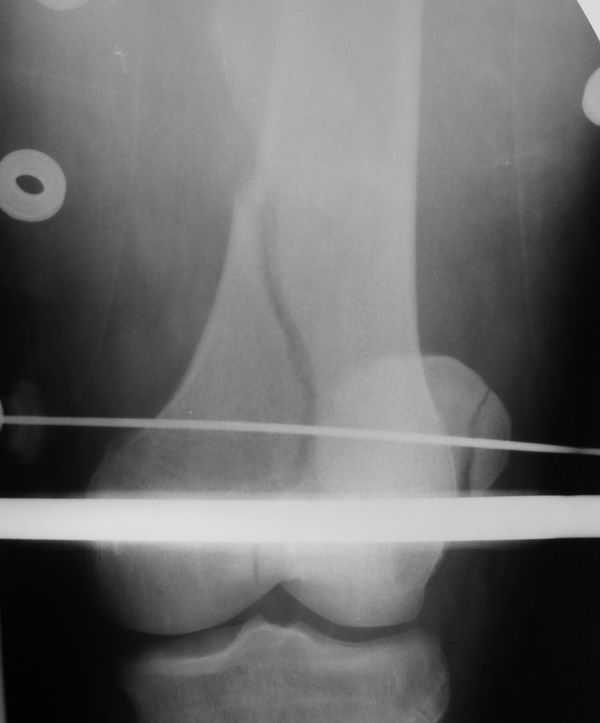

Уважаемые коллеги! Поступил пациент 46 лет после автоаварии от 3.01.

Лечился в ЦРБ. К нам поступил вчера. Имеется оскольчатый перелом диафиза левого бедра, перелом медиального мыщелка, краевой перелом надколенника. У нас, кроме того, выявили перелом шейки бедра. Перелом закрытый, имеется рана в в/3 голени(ниже уровня бугристости б/берцовой кости)без признаков инфицирования.Планируем закрыто фиксировать мыщелок и надколенник винтами, затем закрыто заштифтовать бедро. Вопрос возник по перелому шейки: что предпочесть - длинный PFN или DFN + DHS на шейку?Буду благодарен за ценные советы.С уважением, Станислав Дмитриев.

Заранее приношу извинения за качество снимков. То что есть - либо из ЦРБ, либо сделано в приемном покое, где дежурят рентгенлаборанты различной квалификации. Завтра постараемся сделать снимки всего бедра на длинные кассеты в 2 проекциях. Сейчас больной на скелетном вытяжении. Состояние стабильное.

Я тоже склоняюсь к такой версии.Перелом практически базальный, тип Пауэлс 3 - однозначно нужна угловая стабильность - ни о каких спонгиозных винтах речи нет. Возраст 46 лет, т.е. достаточно молодой - насчет ас. некроза. Накладку DHS вероятно придется ставить монокортикально - штифт получается до малого вертела. Померили расположение имплантов - что называется "стык в стык".